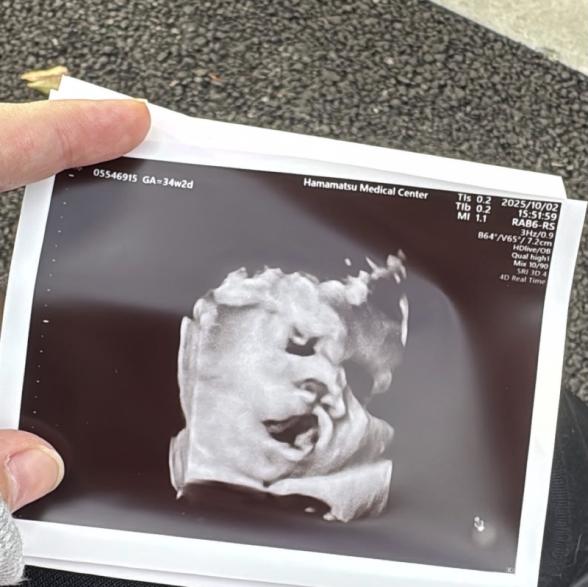

現在妊娠9ヶ月です

前回の検診の時にあくびしてるねって言われたんですが

口唇裂に見えてしまい色々調べった結果余計に不安になってしまいました

お子さんのエコーの見え方についてご心配なのですね。

お写真からですと、一瞬のお子さんの動きを止めているので、なかなかはっきりとしたことは明言できませんが、万が一お子さんの口唇口蓋裂があった場合には、必ずママさんに指摘があると思いますよ。今まで健診で一度も指摘されたことがないのでしたら、ここからの経過の中で口唇口蓋裂になるということはまずないと思いますし、異常はないとご判断いただいて問題ないように思いますよ。